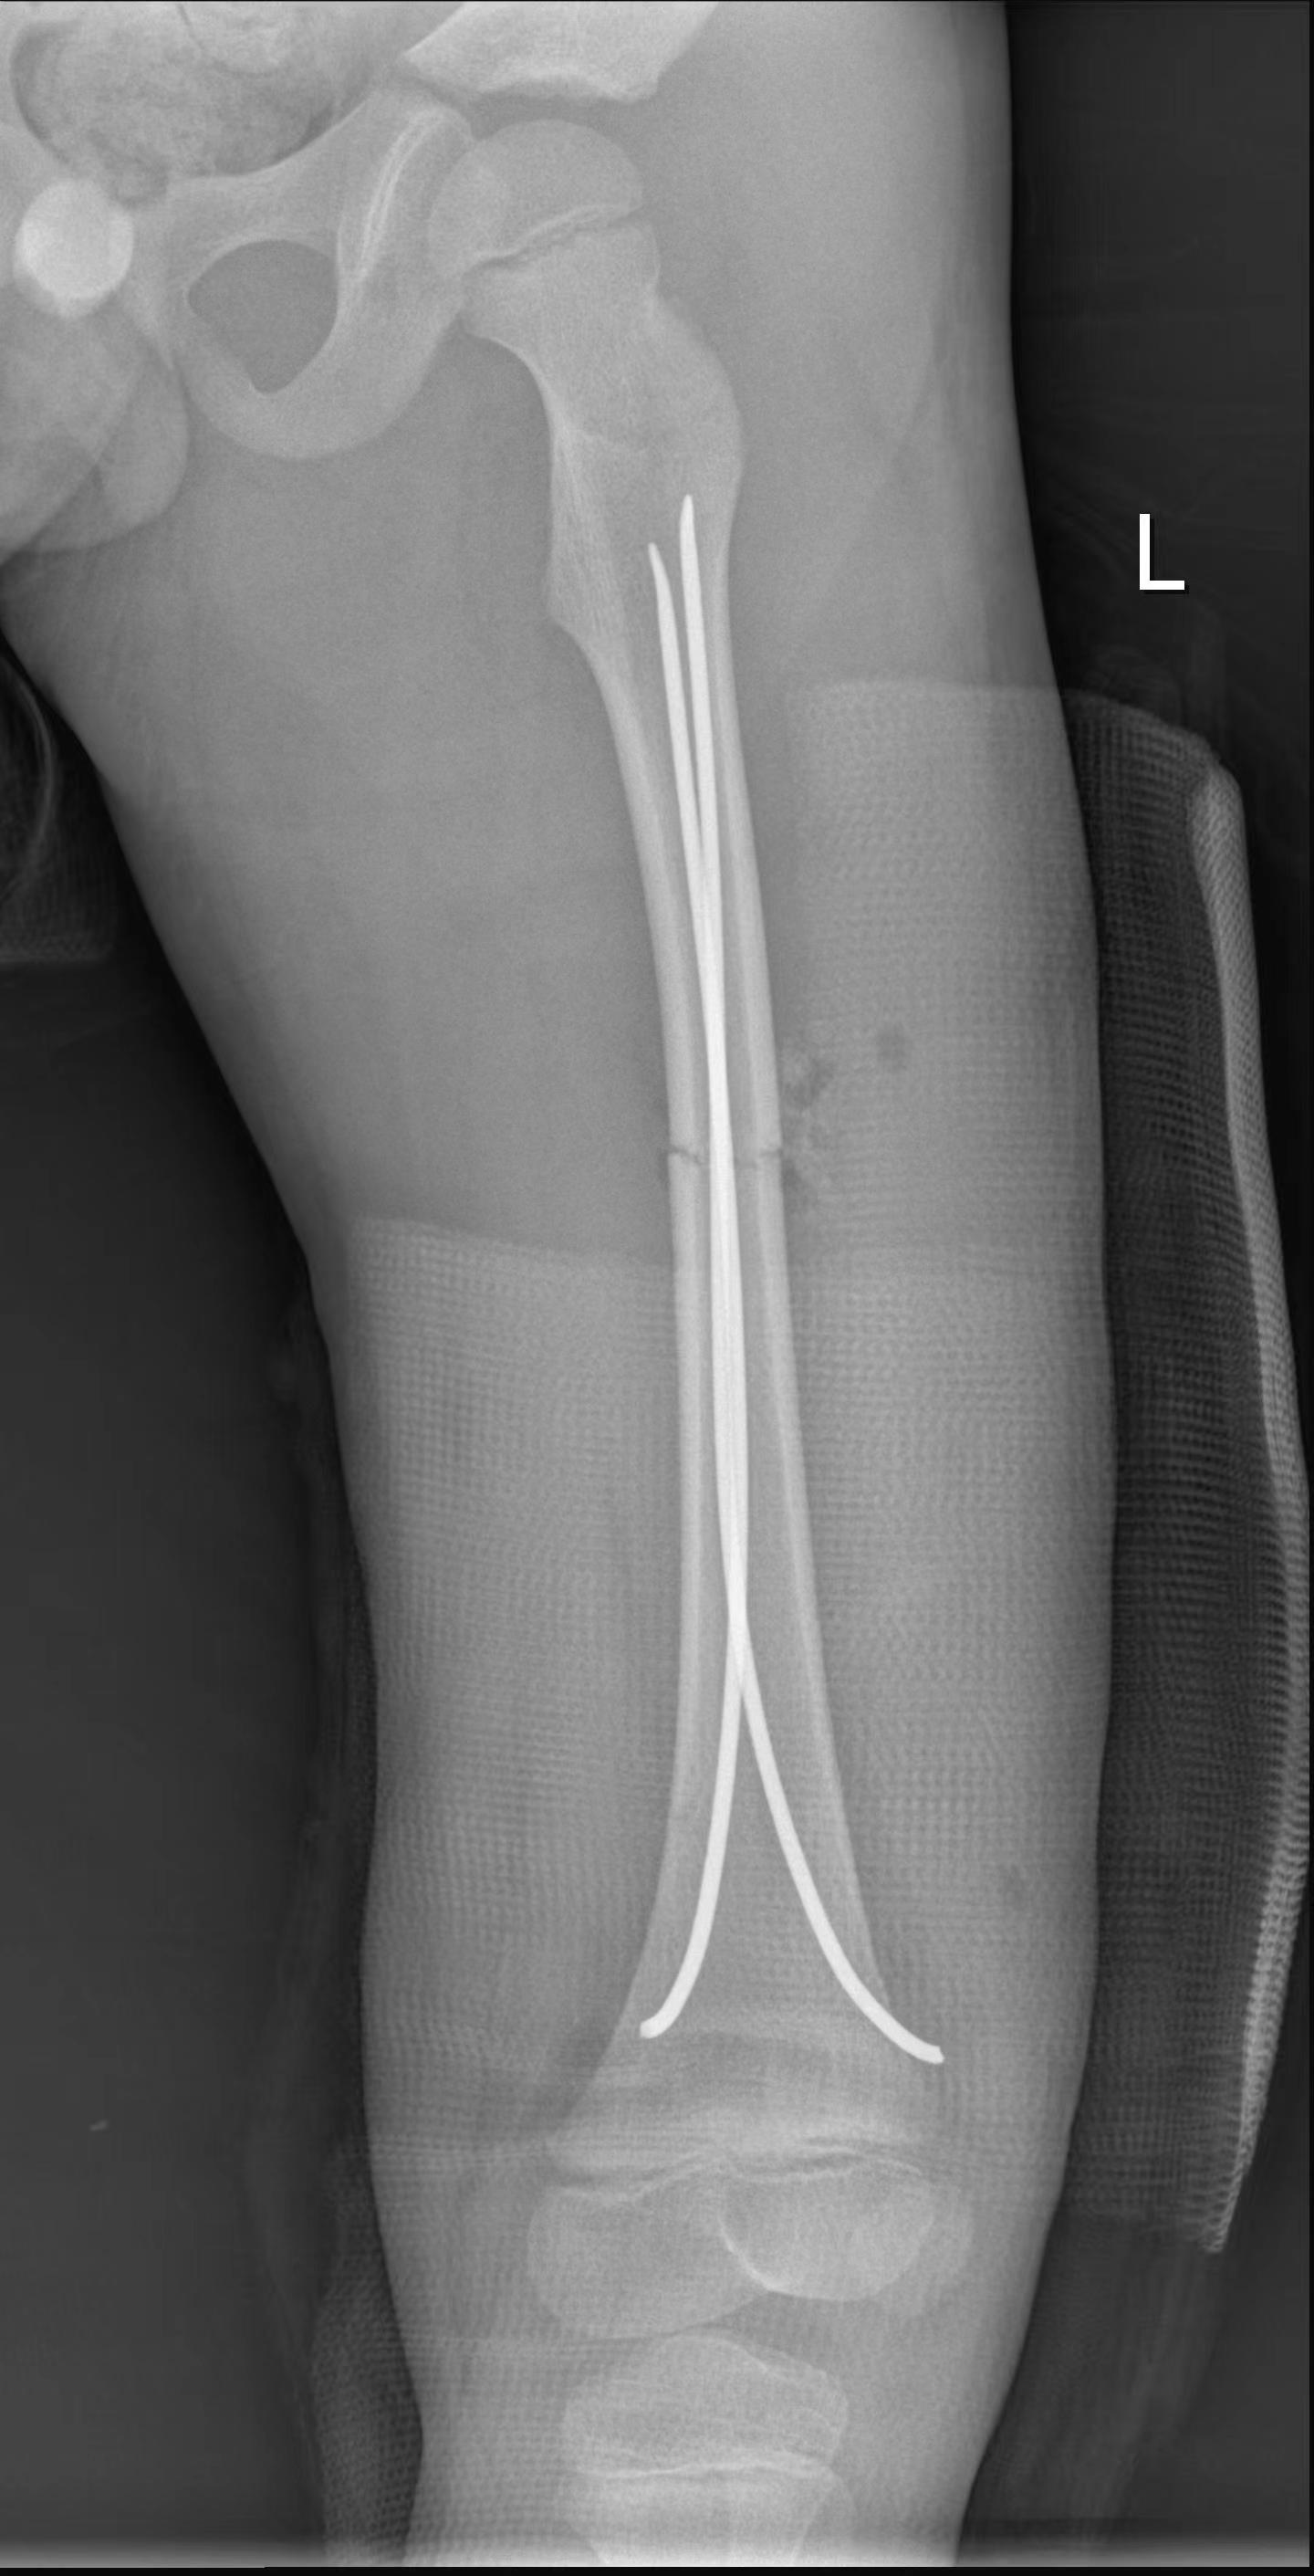

完善各项术前准备工作后,在李杨主任指导下由袁岭副主任医师主刀,开始为患儿实施左股骨干骨折微创撬拨复位弹性髓内针内固定手术。术中,医生通过股骨远端两个约1cm手术切口,将两枚弹性髓内针精准置入股骨髓腔内,顺利完成了复位和固定。乐乐骨折部位仅留下一个直径约0.5cm大小的撬拨复位通道,手术时间短,术中出血量极少,术后骨折即刻得到稳定,在半髋肢具或石膏保护下,术后患肢很快就能进行不负重功能训练,护理非常方便,复查骨折断端对位对线良好,畸形纠正。全家人都对湘南学院附属医院骨二科团队感到非常满意,乐乐顺利康复出院的当天,乐乐奶奶对医务人员激动地说:“我孙子是不幸从楼上掉下来,幸运的是碰到了这么优秀的医师团队,真的非常感谢您们!”